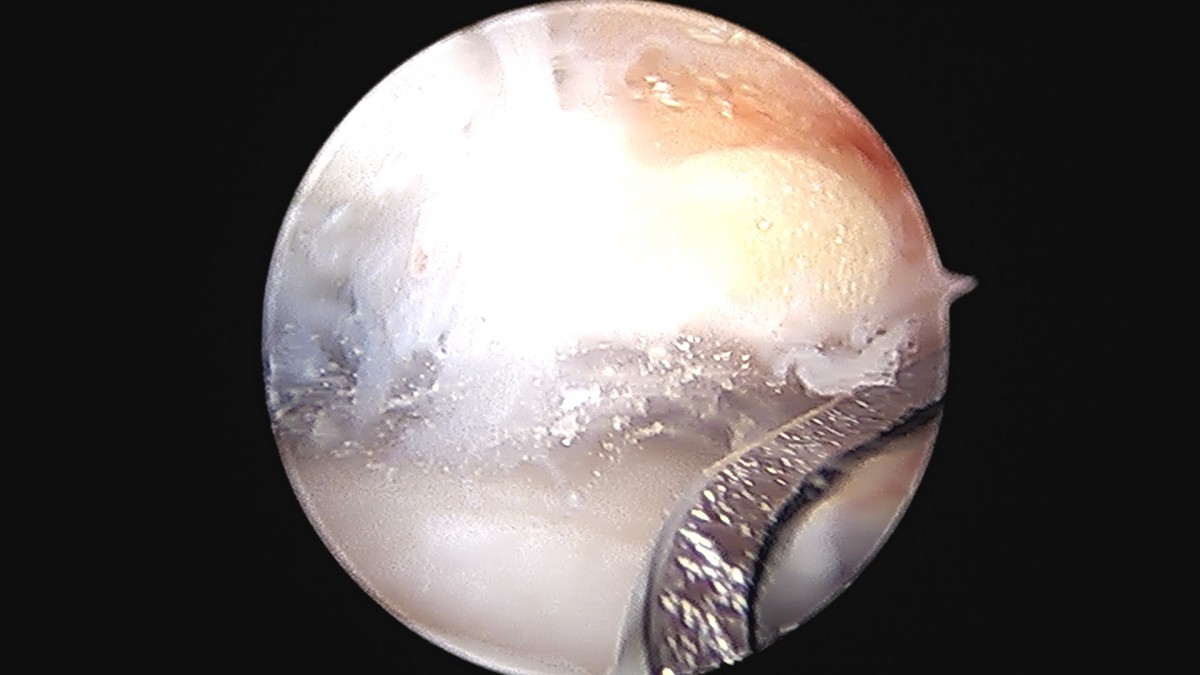

정지영원장님 발목 변연절제술 권공O 환자

dae765e4d9ac96aee867c9d6292d8784_1758009856_846.jpg